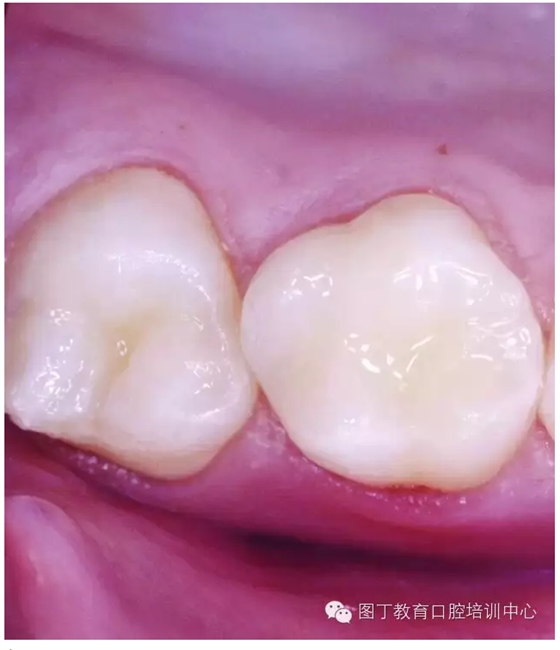

窩溝封閉前后

窩溝封閉后